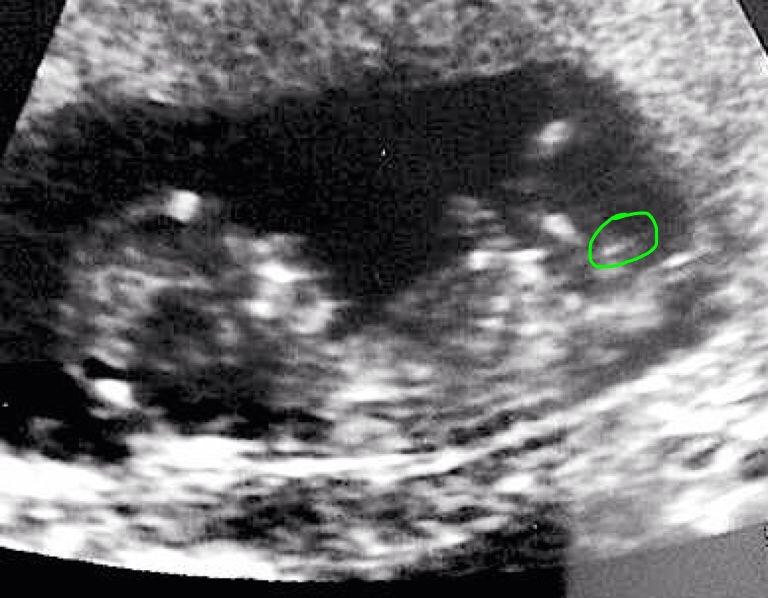

Attachment 18962

If it's an abdominal U/S I'll say girl because gestational sac is pretty much where mine was and I'm having a girl. If internal then it's a boy.

The nub looks very girlie. x

Both of these were abdominal. :)